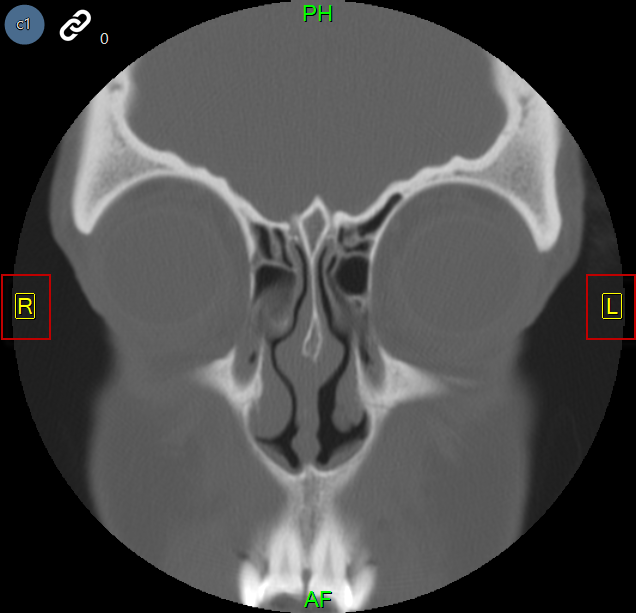

The images below represent a sinus CT and a Mammography that have Auto-Orientation applied.

The auto orientation feature overrides the default patient orientation, as defined by the modality, and applies a user-defined orientation. When auto orientation is applied to an image, the patient orientation markers are force to appear on the image and are displayed in yellow.